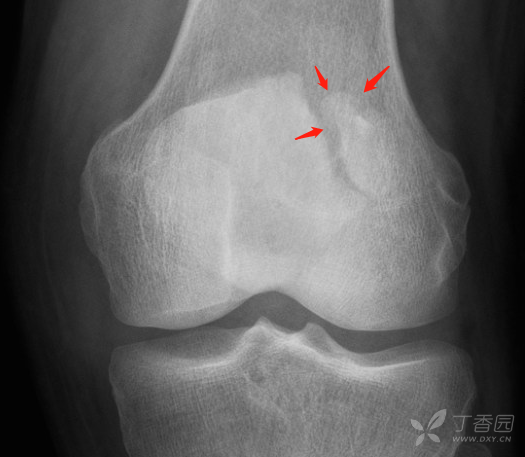

典型骨病系列 13 (二分髌骨 vs 骨折) [病例帖]